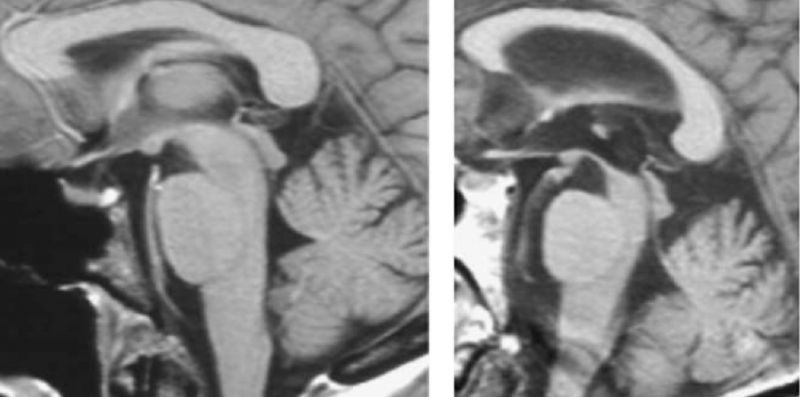

A gauche : IRM cérébrale normale. A droite : IRM cérébrale démontrant un "signe du colibri" (atrophie mésencéphalique et élargissement du quatrième ventricule) caractéristique d'une paralysie supranucléaire progressive.

| actuel | 17 février 2016 à 20:41 |  | 902 × 448 (283 kio) | Dr Shanan Khairi (discussion | contributions) | A gauche : IRM cérébrale normale. A droite : IRM cérébrale démontrant un "signe du colibri" (atrophie mésencéphalique et élargissement du quatrième ventricule) caractéristique d'une paralysie supranucléaire progressive. |